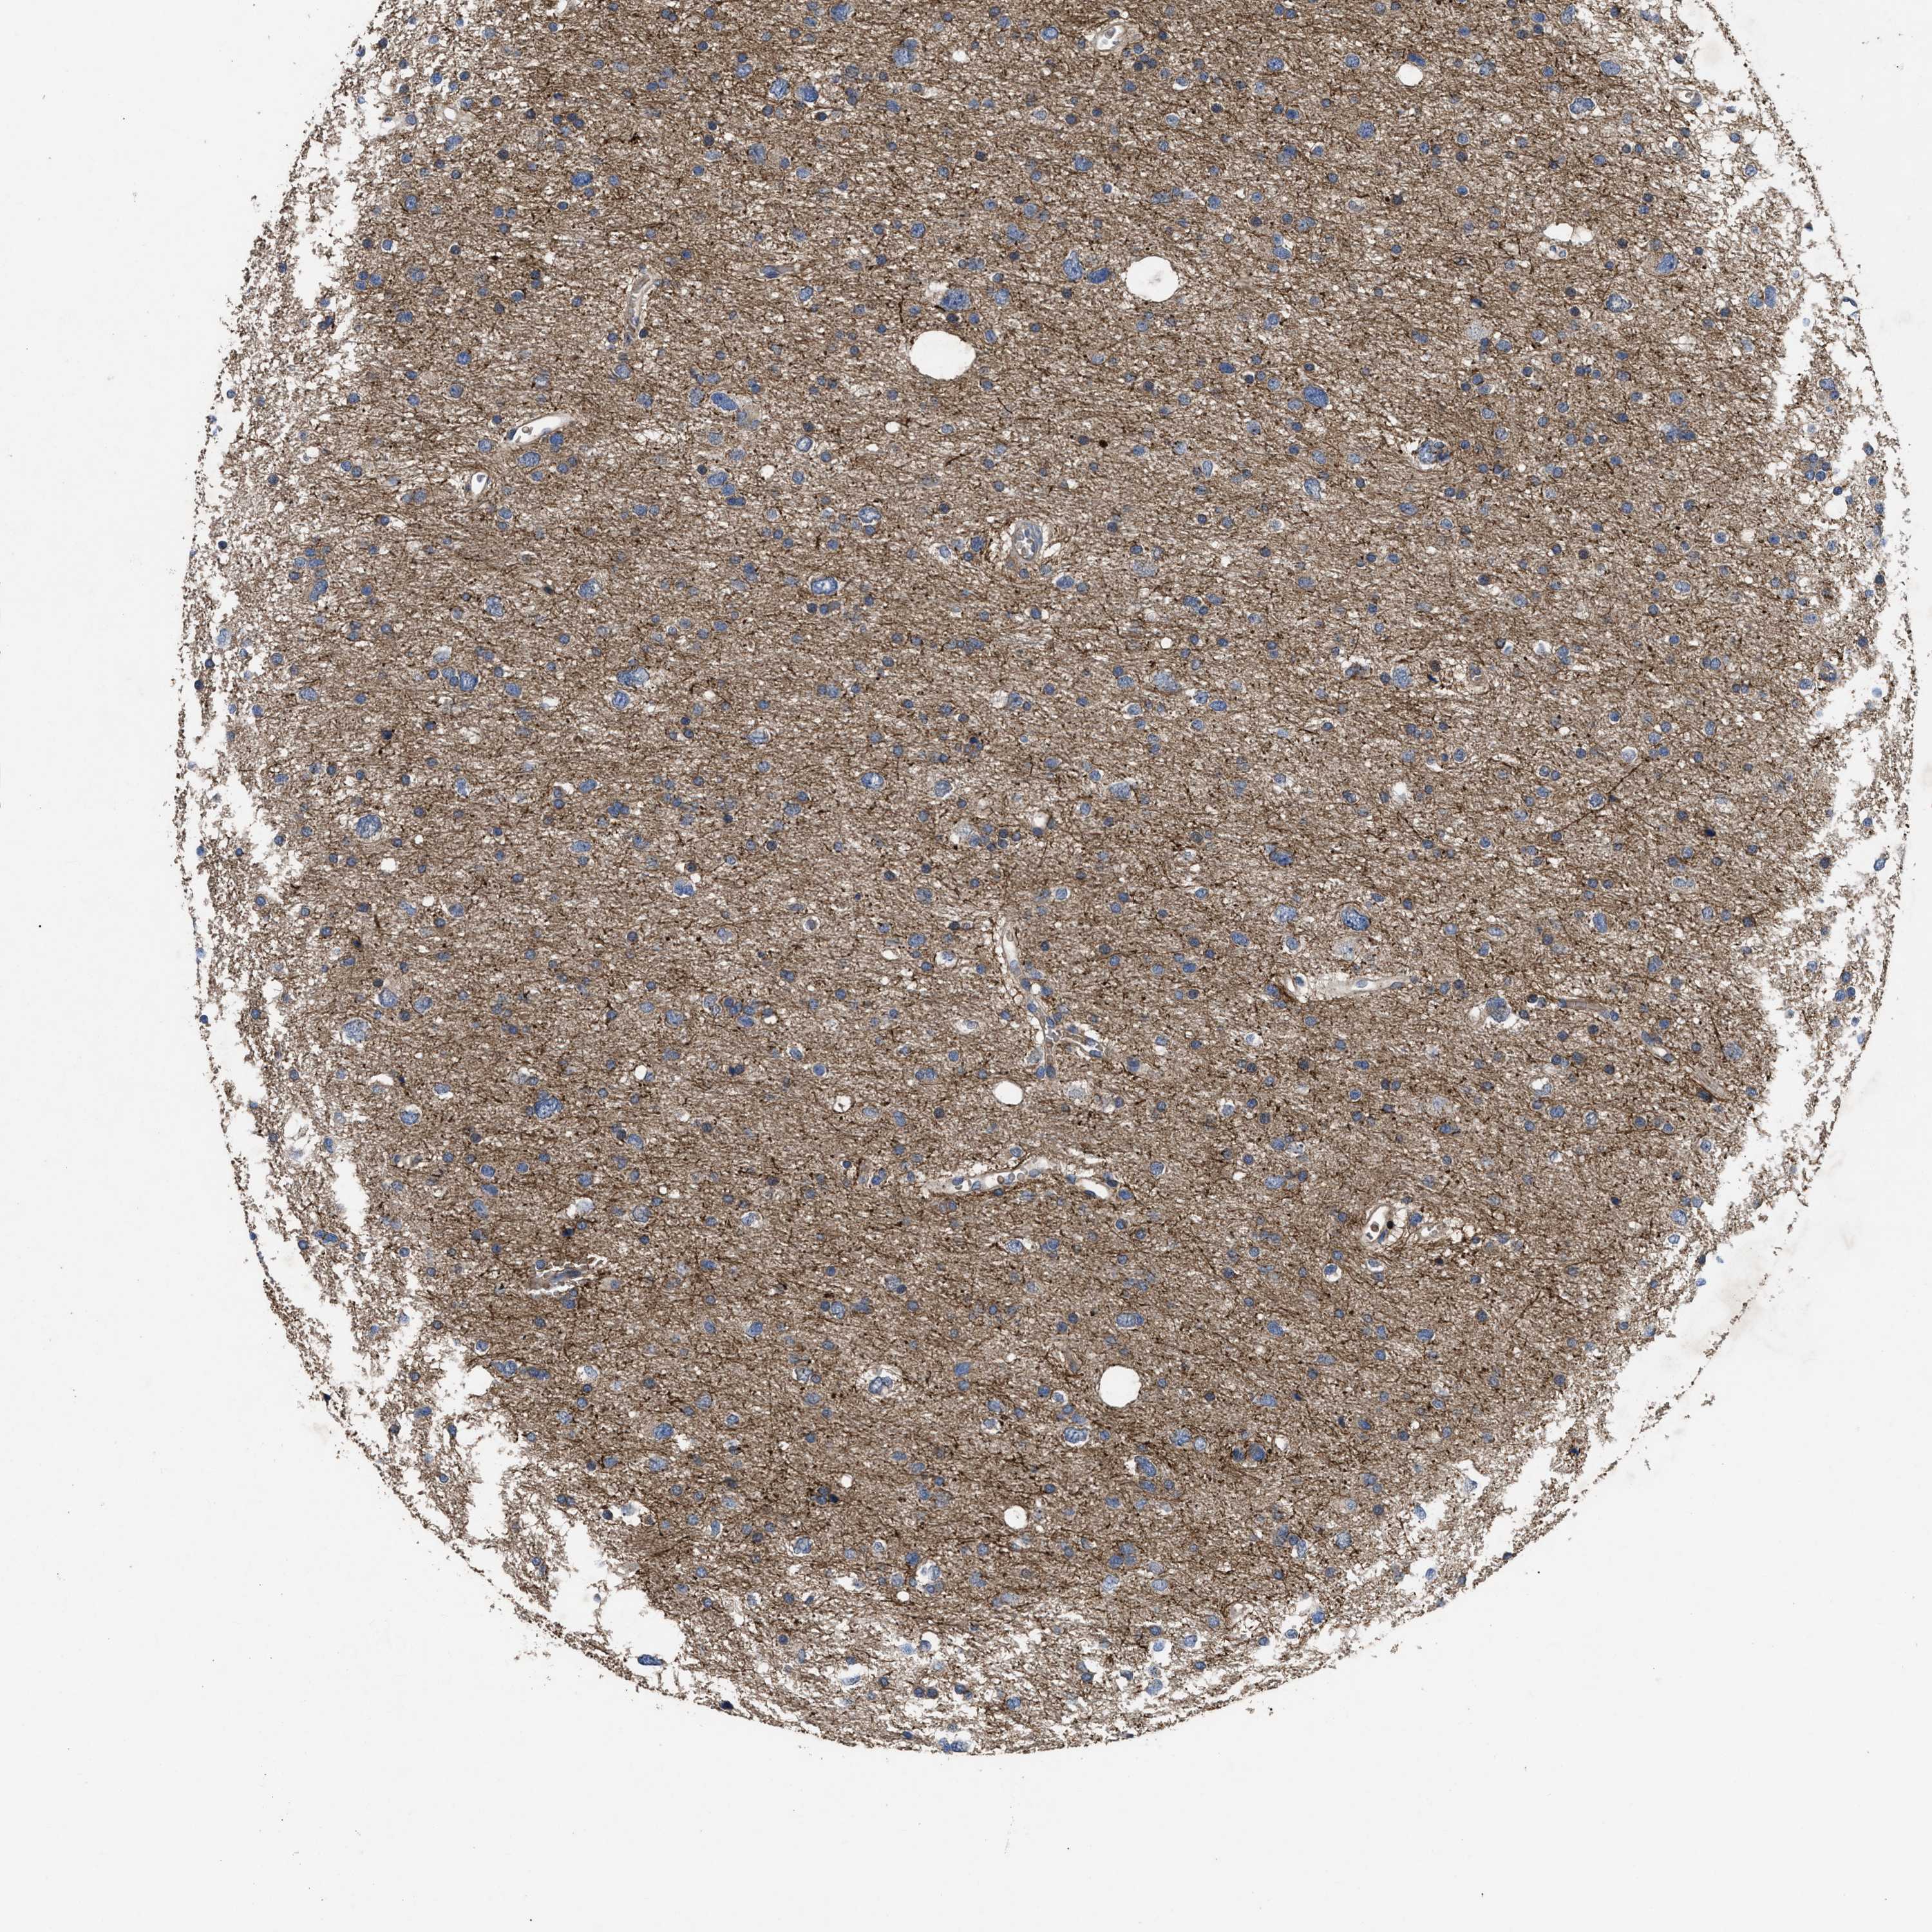

GLIOMA - Protein expressioni

A mouse-over function shows sample information and annotation data. Click on an image to view it in a full screen mode. Samples can be filtered based on level of antibody staining by selecting one or several of the following categories: high, medium, low and not detected. The assay and annotation is described here.

Note that samples used for immunohistochemistry by the Human Protein Atlas do not correspond to samples in the TCGA dataset.

Antibody stainingi

Antibody staining in the annotated cell types in the current human tissue is reported as not detected, low, medium, or high, based on conventional immunohistochemistry profiling in selected tissues. This score is based on the combination of the staining intensity and fraction of stained cells.

Each image is clickable and will lead to virtual microscopy that enables deeper exploration of all samples and also displays staining intensity scores, fraction scores and subcellular localization as well as patient and tissue information for each sample.

Antibody HPA018162

Staining

High

Medium

Low

Not detected

Intensity

Strong

Moderate

Weak

Negative

Quantity

>75%

75%-25%

<25%

None

Location

Nuclear

Cytoplasmic/membranous

Cytoplasmic/membranous,nuclear

Glioma, malignant, High grade

Glioma, malignant, Low grade